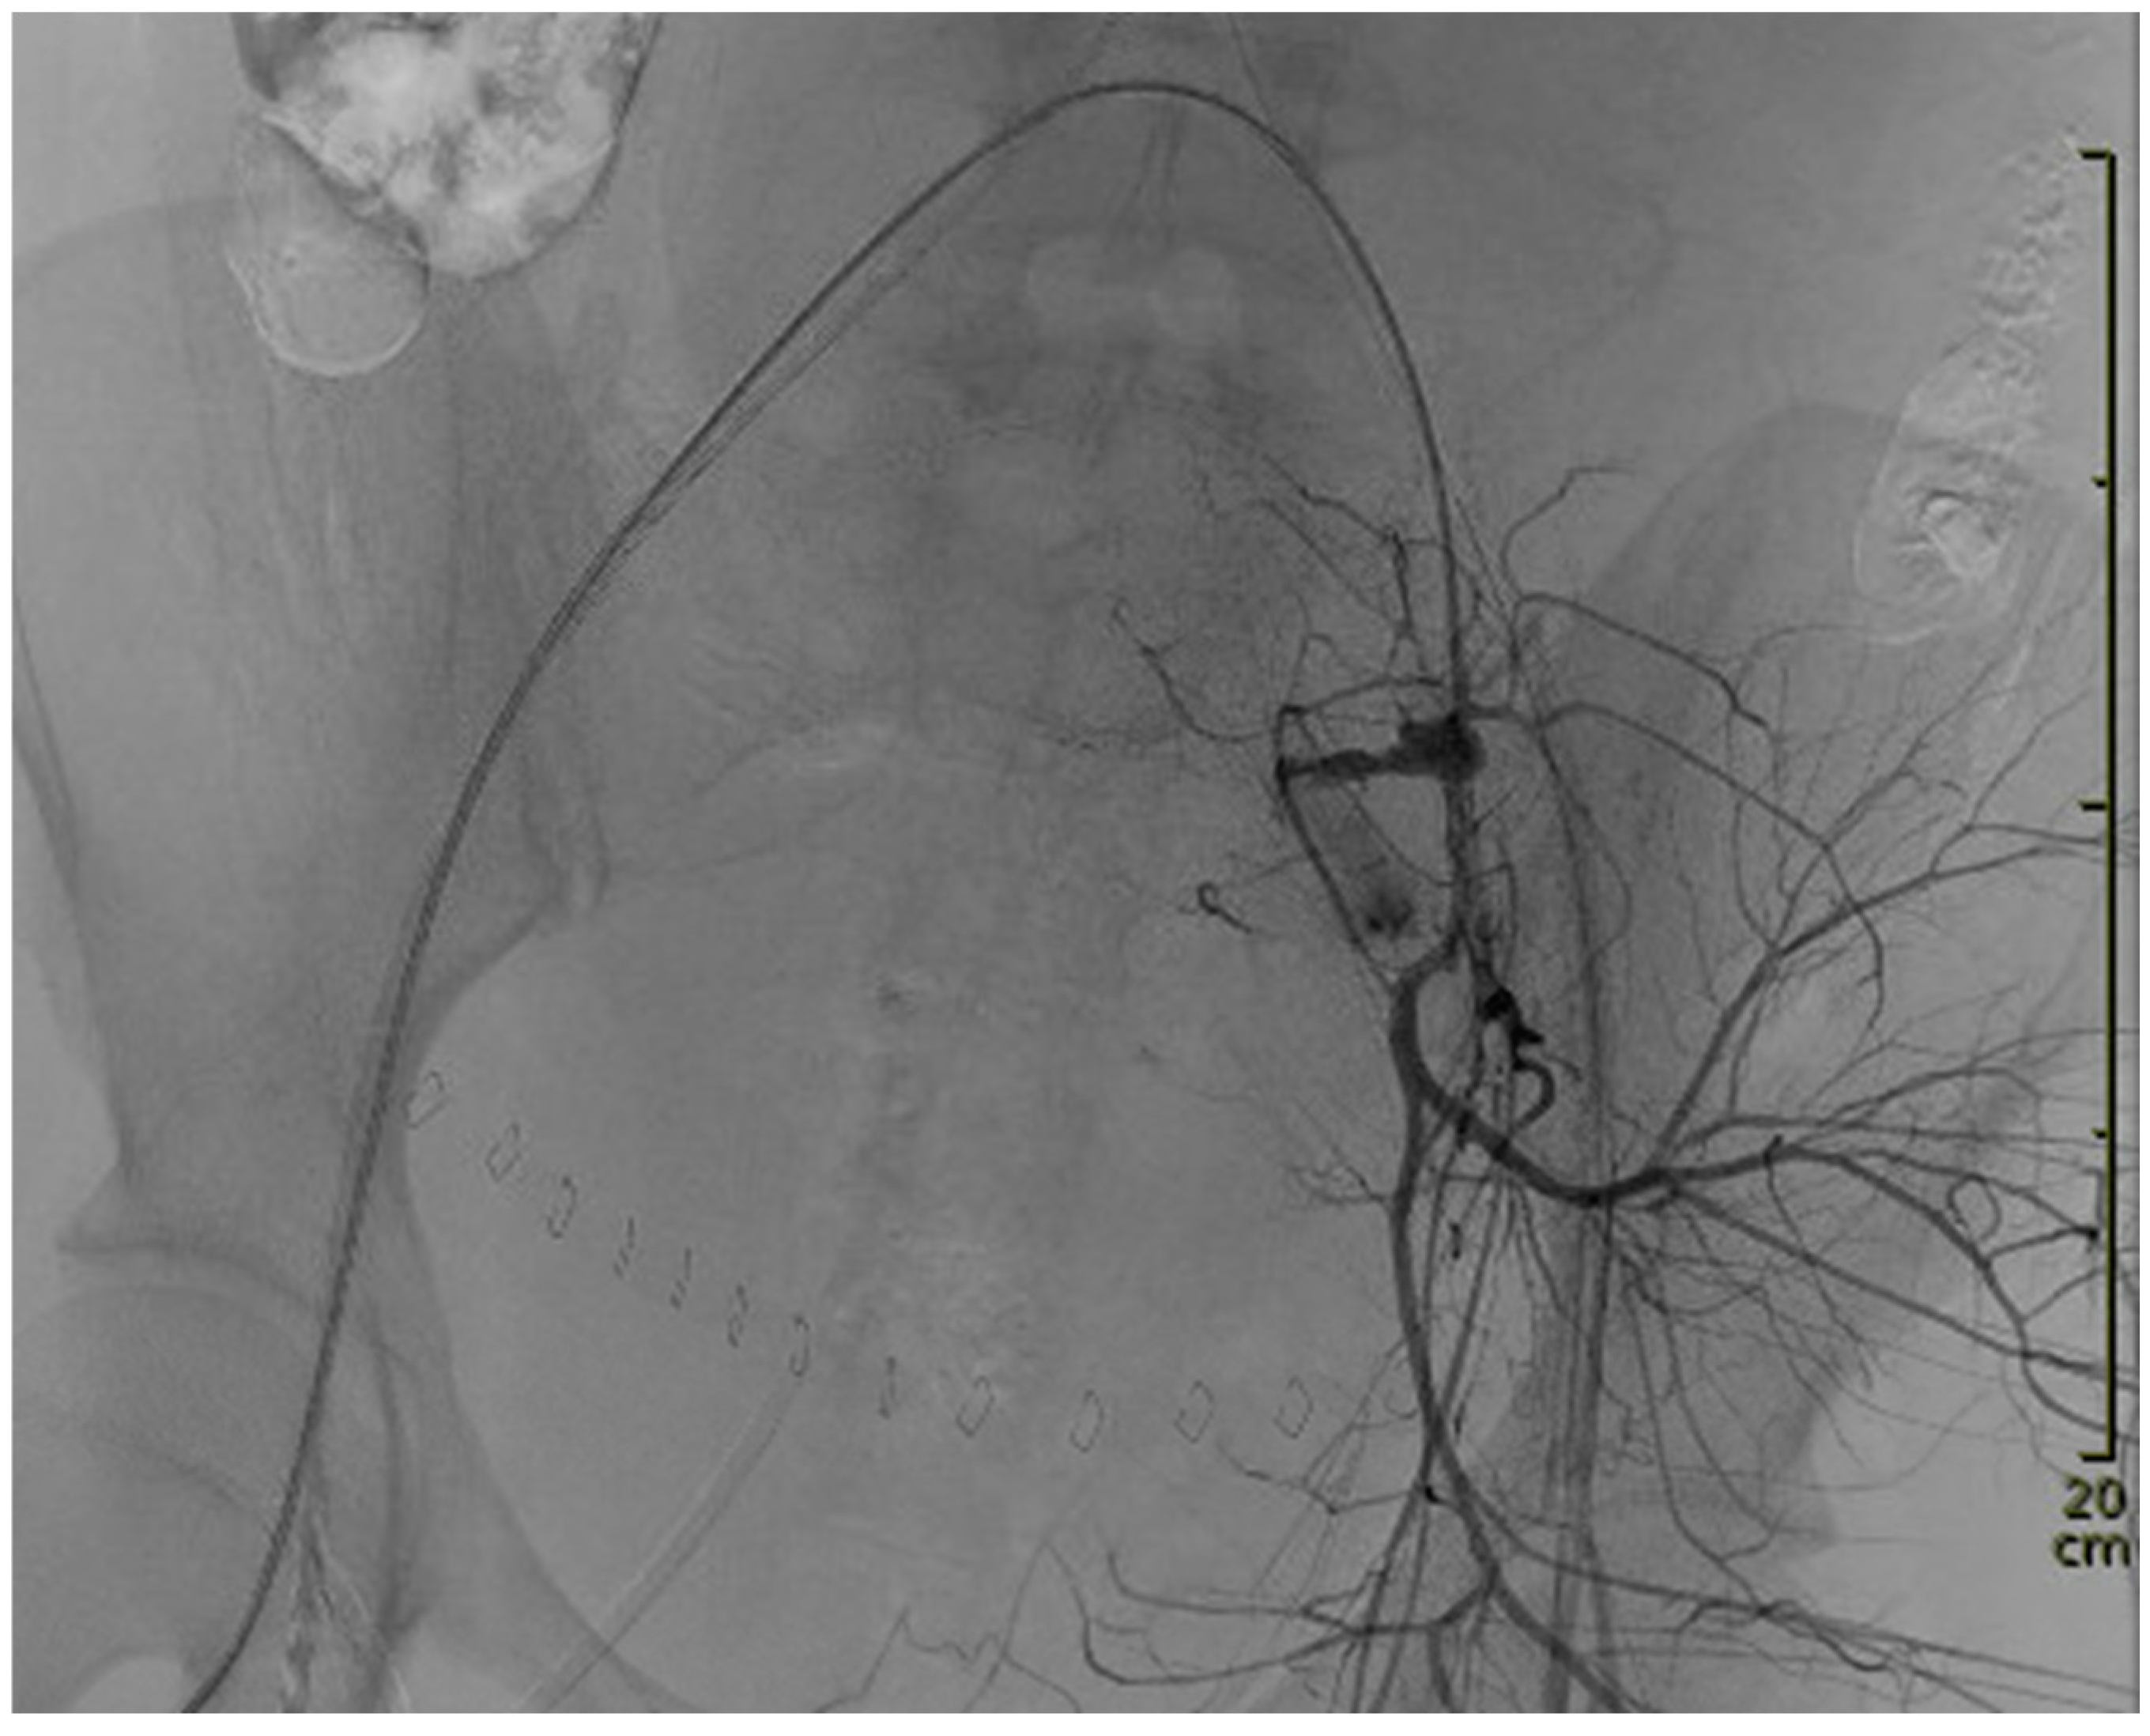

Thereafter, the hemodynamically stable woman was transferred to the intensive care unit for further observation, with a continuous uterotonic infusion and antibiotic prophylaxis. The approximate duration of the intermittent aortic occlusion was approximately 70–75 min. Forty-three minutes after the REBOA balloon placement, and within seven minutes after the start of the angiography, the site of bleeding was localized, and embolization had begun. Perfusion was allowed intermittently by deblocking the REBOA balloon after initial bleeding control for diagnostic angiographic imaging and verification of hemostasis. There was no standardized inflation–deflation regimen of the balloon at the end of the procedure. The regimen was determined instead based on bleeding control and clinical stabilization of the patient. The final deblocking of the REBOA balloon was conducted slowly, over five minutes, and under the control of clinical parameters and angiographic signs of rebleeding.

Within 24 h, the patient developed an anuric acute kidney injury (AKI III). Sonographically, the bladder could not be visualized with the Bakri® balloon in place, but a hydronephrosis grade I was seen on the right side. A pre-existing pregnancy-associated hydronephrosis is very common on the right side, although in this case it was not previously described. The Bakri® balloon and Celox™ gauze were removed after approximately 24 h (in accordance with German-speaking guidelines, the Bakri® balloon is routinely left in place for 24 h [1]) and the hydronephrosis was slightly regressive. A timeline of the events is presented in Figure 3.

Figure 3. Timeline of events from onset of bleeding. ICU intensive care unit; REBOA resuscitative endovascular balloon occlusion of the aorta; TAE transcatheter arterial embolization; TXA tranexamic acid.